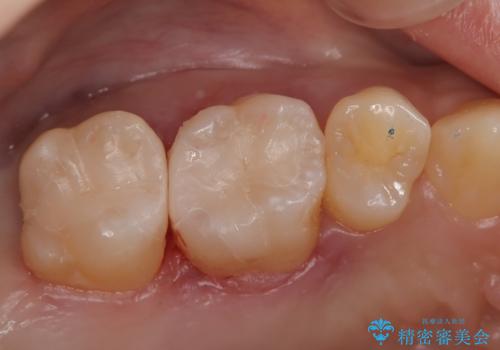

根管治療時に穿孔部位を認め、MTAにて修復し、分岐部の歯周ポケットおよび骨欠損に対しては、再生治療を行うことで、正常な歯周状態の獲得ができました。

歯冠修復はオールセラミッククラウンで行なっております。